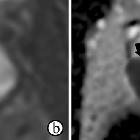

Three morphological MRI patterns have been described which are diffuse, nodular (tumor-like), and cystic with mural nodule .

Signal characteristics include

- T2: affected regions hypointense

- C+ (Gd): no enhancement following Gd-DTPA